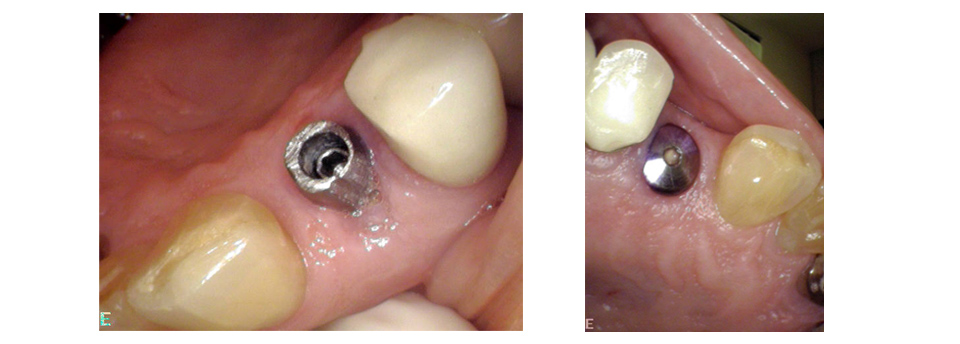

Missing teeth can be a nuisance, both cosmetically and functionally; you may feel self-conscious about a gap in your smile, and that gap will almost certainly cause problems with biting and chewing. While there are several procedures dentists use to fill in gaps left by missing teeth, dental implants are by far the most natural-seeming in form and function. A dental implant is nearly indistinguishable from a natural tooth and can last a lifetime with proper maintenance. Click here to find out more.